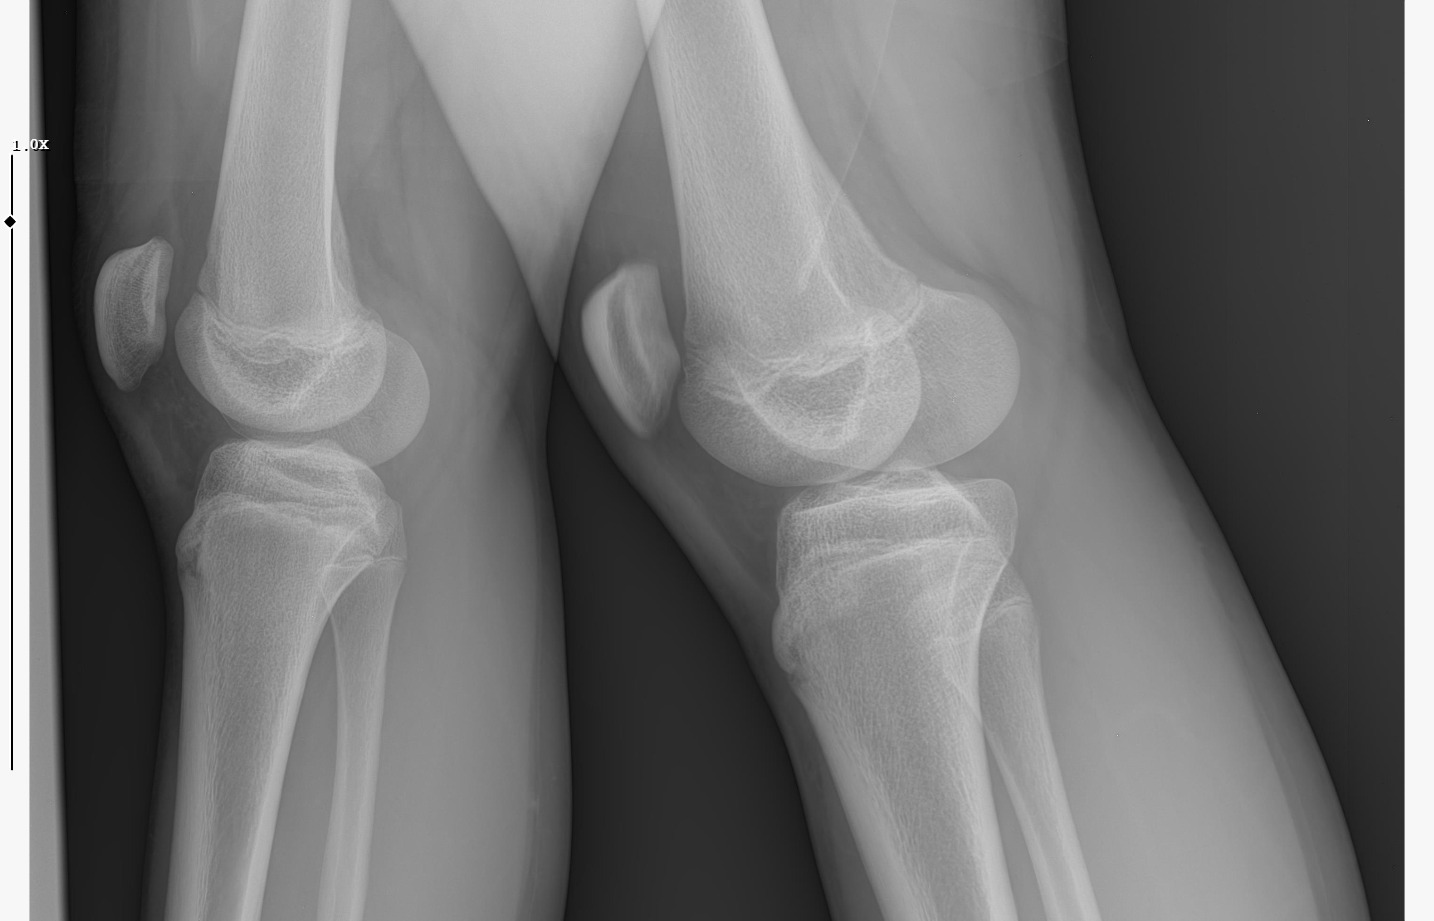

doktor bi sik bilmiyodur büyük ihtimalle plakları buraya at biz bakak

bide bir sekilde hgh temin et babandan kısasın uzama olasılığın çok daha fazla gh ile,şuan ona paran yoksa da biriktirmeye başla aromasin kullan

IMG 5959

röntgeni atar mısın?

böyle ne diyorsun yaşım genc bu arada

Attachments

• WhatsApp Image 2026-01-07 at 00.31.08 (4).jpeg

WhatsApp Image 2026-01-07 at 00.31.08 (4).jpeg

161.8 KB · Views: 0

• WhatsApp Image 2026-01-07 at 00.31.08 (3).jpeg

WhatsApp Image 2026-01-07 at 00.31.08 (3).jpeg

104.8 KB · Views: 0

• WhatsApp Image 2026-01-07 at 00.31.08 (1).jpeg

WhatsApp Image 2026-01-07 at 00.31.08 (1).jpeg

140.5 KB · Views: 0

• WhatsApp Image 2026-01-07 at 00.31.08.jpeg

WhatsApp Image 2026-01-07 at 00.31.08.jpeg

138.6 KB · Views: 0

kapanmaya baslamıs ama cok yakın degil

kemik yaşın 15 gibi 15'e çok yakın

anne baba boyun ve yaşını bilmiyorum sadece bu bilgilerle 171-175 arası diye tahmin ediyorum röntgen ile.

normalde anne babana göre 171-176 olman gerek zaten. kemik yaşın ve şuanki boyun ile yapılacak tahmin anne baban ile yapılabilecek tahminle nerdeyse birebir aynı yani büyük ihtimal o civarlar olursun bence